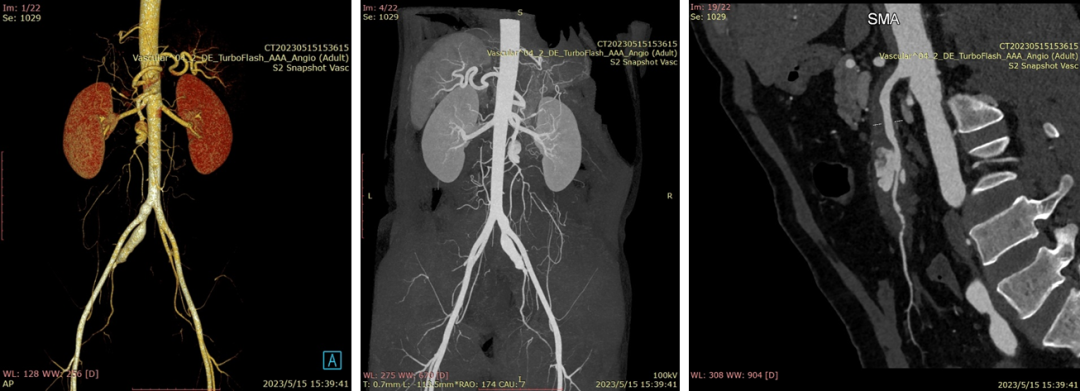

20230515CTA(保守治疗2周我院复查)

20230524DSA夹层动脉瘤

20230524DSA:VB支架植入

20230524DSA:仍有造影剂进入假腔

20230524DSA:再次送入VB

20230530CTA(术后1周):夹层动脉瘤隔绝完全

20230913CTA(术后14周):血肿吸收完全